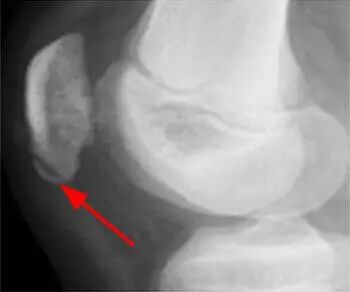

图6-1:一张侧位X线片显示,一名患有慢性膝前部疼痛的12岁男性跑步者的髌骨下极存在一个小的骨化病灶(箭头所示)。

图6-2:在相应的脂肪抑制T2加权矢状位图像上,髌骨下极内的骨髓水肿(箭头所示)清晰可见,这与Sinding-Larsen-Johansson 病相符。https://radsource.us/developmental-variants/